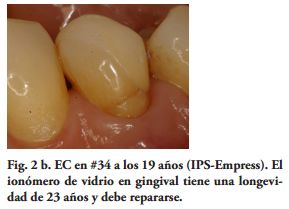

Mientras, en estudios clínicos y de laboratorio, los cementos resinosos de polimerización química y dual, tuvieron un mejor comportamiento que los fotopolimerizables y los de autograbado (38-44). Sin embargo, utilizando unidades de curado LED de alta potencia y aumentando el tiempo de exposición, a través de materiales cerámicos con diferentes espesores, recientes investigaciones de laboratorio han encontrado mayor grado de conversión y después de 24 horas, mayores valores de microdureza, en cementos resinosos fotopolimerizables y duales (45,46). Por lo tanto, los procedimientos clínicos y los cementos utilizados, pudieron haber influido en el Éxito Clínico obtenido (90%) (Figs. 1c, 2b, 3b, 4b).

Al momento del examen, 10 (90.9%) EC estaban en función en 10 pacientes. Un molar 26, restaurado con EC, se perdió por enfermedad periodontal después de 12 años y 9 meses en función. Ninguna restauración se desprendió, no hubo recidiva de caries y al examen radiográfico no se observaron lesiones patológicas en los 10 DPET en función (Figs. 1a,1d; 2c; 3c,3d; 4c).